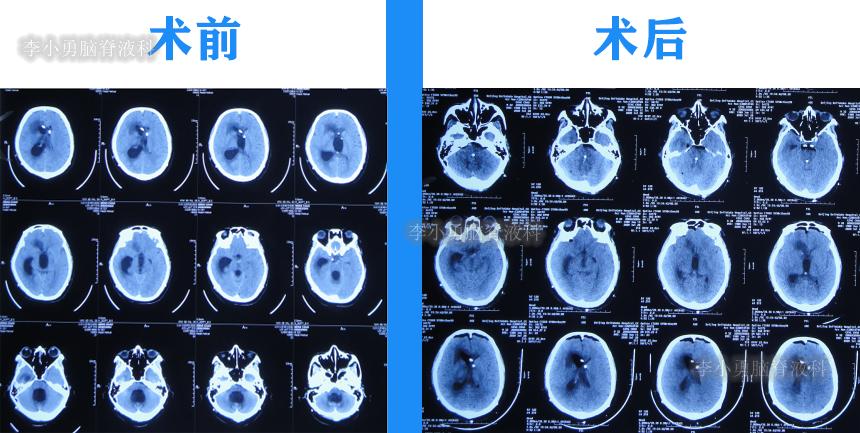

于2020年10月21日(住院治疗139天),进行了侧脑室和四脑室腹腔分流术。

于2020年10月30日(住院治疗148天),查头颅CT示脑室未见异常(图-32)。

图-32:2020年10月30日头颅CT

2020年11月3日(住院治疗152天)出院,出院时:意识变清,自己站立变稳,能自己走路,双眼对视有好转(图-33)。

图-33:2020年11月3日出院时

2022年4月28日(住院治疗193天)出院,出院时:意识清楚,言语交流正常,肢体活动、走路基本正常(图-50);查头颅CT示未见异常(图-51)。

图-50:2022年4月28日出院时

图-51:出院时头颅T